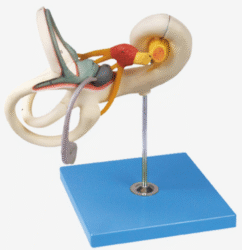

ATL-114 ADVANCED EAR INPECTION SIMULATOR SOFT

ATL-115 ADVANCED EAR IRRIGATION SIMULATOR SOFT

ATL-116 ADVANCED EAR DIAGONOSTIC SIMULATOR SOFT